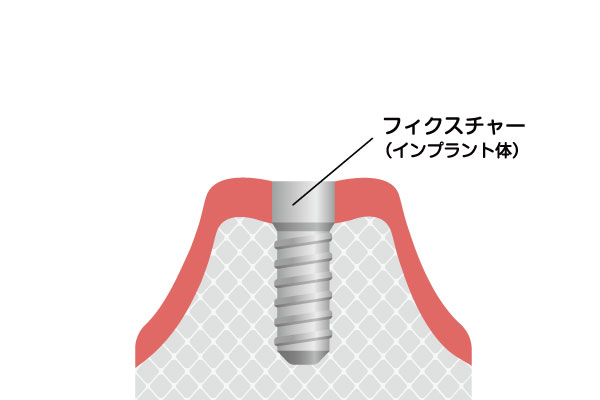

インプラント治療は、失った歯を補うために人工の歯根(歯の根っこ)をあごの骨に埋め込む治療法です。インプラント体は通常チタンでできており、チタンが骨と結合する性質があることから、強固で安定した基盤が作られ、その上にアバットメント(土台)を接続し、上部構造(人工歯)を装着します。これにより、見た目も自然で、機能的にも快適な歯を再建することができます。インプラントは自分の歯とほぼ同じように感じられ、他の歯への負担も最小限に抑えられます。

インプラントの埋入手術

治療計画に基づいて、インプラントをあごの骨に埋め込む手術を行います。手術は局所麻酔で行い、痛みを感じにくいようにします。手術後、インプラントがあごの骨としっかり結合するまで、数ヶ月の治癒期間を設けます。